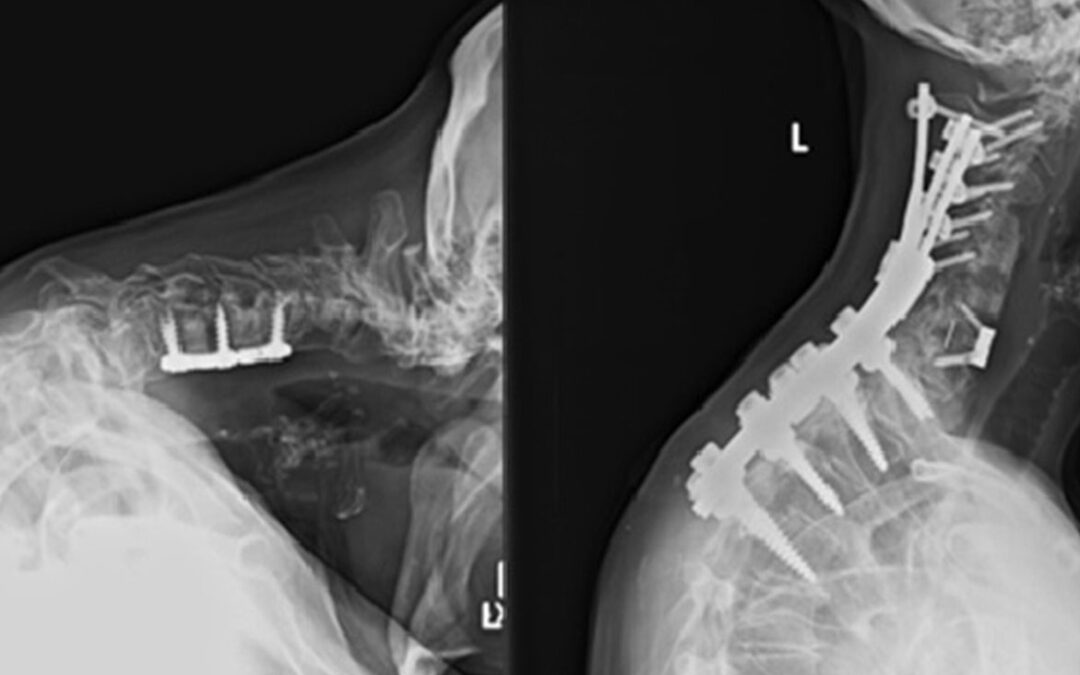

Cervical deformity refers to abnormal alignment or curvature of the cervical spine. This condition can result from trauma, degenerative disease, congenital abnormalities, or previous surgeries. Left untreated, cervical deformity symptoms can lead to chronic pain,...